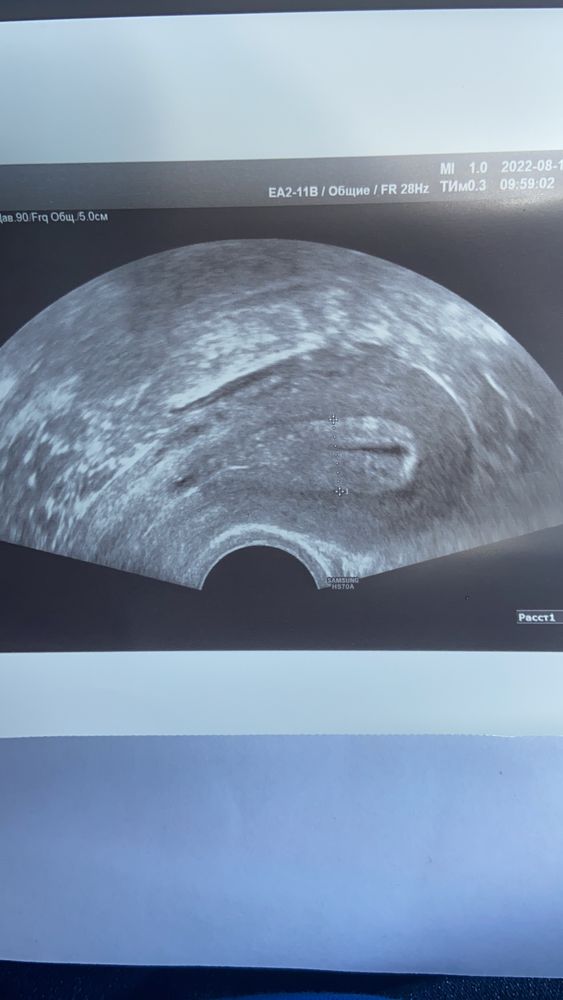

Ну просто по статическому снимку непонятно. Это не беременность точно, учитывая результат ХГЧ. Возможно киста, возможно полип, или ещё похоже на то, что менструация начнётся вот со дня на день. Узи надо будет переделать на 5-7 день цикла, чтобы исключить патрологию эндометрия. А сейчас, если сегодня-завтра месячные не начнутся, я бы обратилась к врачу, что выписали таблетки типа Норкалута или Дюфастона

В матке нет ничего. Мбчто то в шейке, но скорейэ то киста чем беременно ть, те если беременно то в шейке то скорей всего она не будет развиваться. Если тест отриц то ждите мес

Ну плодного яйца в матке не видно, судя по снимку 🤷🏼‍♀️ При вашем хгч и не увидят пока.